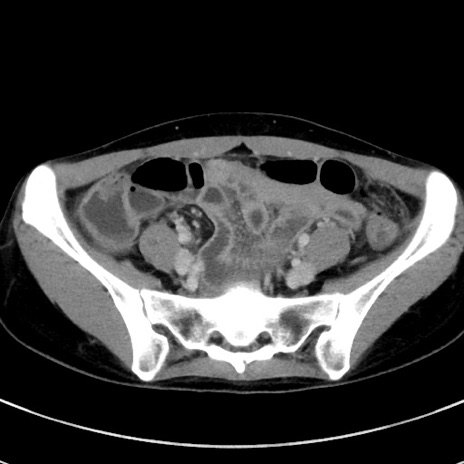

症例17(横断像)

冠状断像

【症例】20歳代女性

【主訴】嘔吐、下腹部痛

【現病歴】昨日夕食後に嘔吐し下腹部痛が出現。本日になっても嘔吐持続し改善しないため来院。

【身体所見】意識清明、BT 37.2℃、BP 108/67mmHg、腹部:平坦、やや硬、下腹部正中から右にかけて圧痛あり、反跳痛軽度あり、tapping pain(+)。

【データ】WBC 13600、CRP 14.94